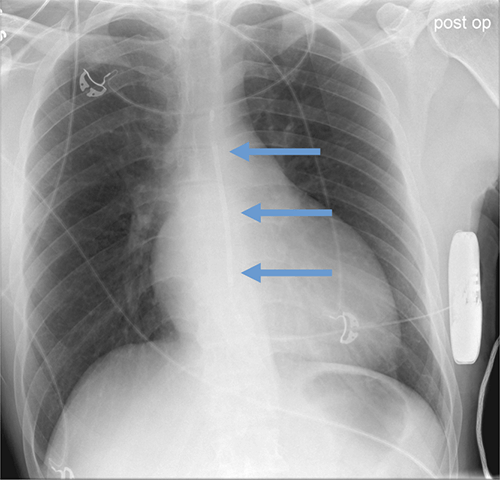

- CEID images with lead types:

Abanded leads plus generator